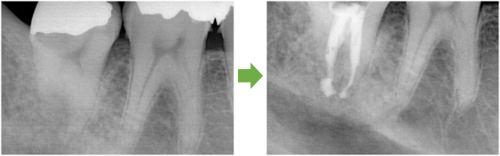

術前

同拡大

抜歯後

抜歯後GBR

GBR後

同拡大像